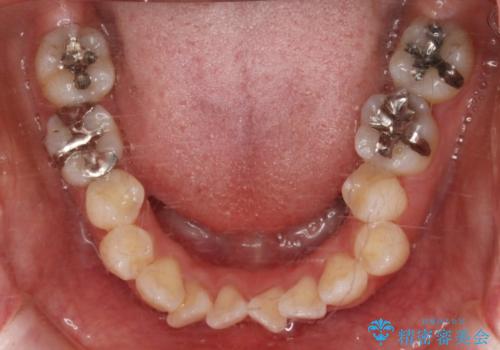

- 前歯のガタつき・噛み合わせの不調を主訴にご来院されました。

患者様のお仕事柄、目立たない装置で矯正したいとのご要望があり、今回はインビザラインを用いて抜歯矯正を行うこととなりました。

本来、抜歯によって得られる大きなスペースのコントロールはワイヤー装置の方が得意とされていますが、こちらの患者様のように犬歯が大きく手前に傾斜していて奥歯の噛み合わせにそれほど問題がないケースではマウスピース装置でも十分にコントロールできることが予測されます。